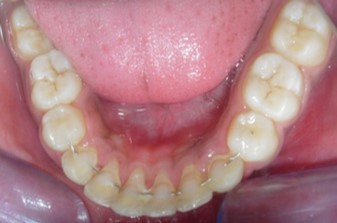

Intraoral assessment. (Figure 1d,Figure 1e,Figure 1f,Figure 1g,Figure 1h).

Figure 1h.Pre-treatment intra-oral-Lower occlusal

Pre-treatment intra-oral-Lower occlusal

The maxillary arch was V-shaped with severely proclined and rotated maxillary incisors with a palatally placed 12. The mandibular arch was U-shaped with severe crowding of mandibular incisors, with 43 partially erupted and buccally placed with transpositioned 42 and 43, with 42 mesiolingually rotated, 33 distolingually rotated and 34 distolingually rotated and buccally placed.

Severe increase in overjet and deep bite were both observed. The maxillary midline coincided with the skeletal midline but the mandibular midline was shifted to the right side by 1 mm. Bilateral maxillary posterior crossbite was also observed. On right side the molar relation was Class I and on the left side it was Class II. The canine relation was Class II on the left side and the curve of Spee was increased.